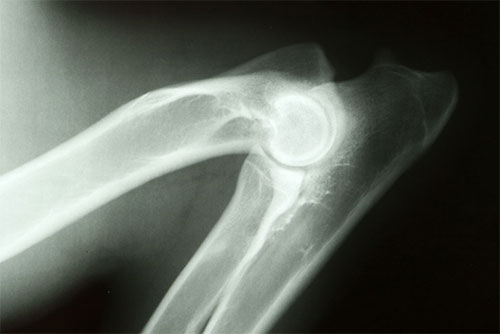

ccs-65-0-39888100-1434408522.jpg"Hip (HD) and Elbow Dysplasia (ED) are two common complex developmental disorders of dogs. In order to decrease their prevalence and severity, the Orthopedic Foundation for Animals (OFA) has a voluntary registry of canine hip and elbow conformation certified by boarded radiologists. However, the voluntarily reports have been severely biased against exposing dogs with problems, especially at beginning period. Fluctuated by additional influential factors such as age, the published raw scores barely showed trends of improvement. In this study, we used multiple-trait mixed model to simultaneously adjust these factors and incorporate pedigree to derive Estimated Breeding Values (EBV). A total of 1,264,422 dogs from 74 breeds were evaluated for EBVs from 760,455 hip scores and 135,409 elbow scores. These EBVs have substantially recovered the reporting bias and the other influences. Clear and steady trends of genetic improvement were observed over the 40 years since 1970. The total genetic improvements were 16.4% and 1.1% of the phenotypic standard deviation for HD and ED, respectively. The incidences of dysplasia were 0.83% and 2.08%, and the heritabilities were estimated as 0.22 and 0.17 for hip and elbow scores, respectively. The genetic correlation between them was 0.12. We conclude that EBV is more effective than reporting raw phenotype. The weak genetic correlation suggested that selection based on hip scores would also slightly improve elbow scores but it is necessary to allocate effort toward improvement of elbow scores alone."